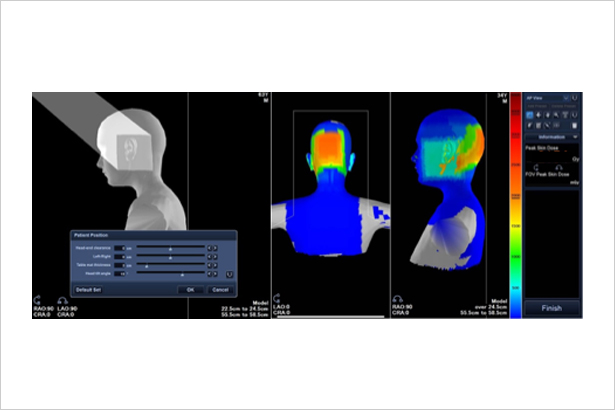

實時顯示患者皮膚接受輻射劑量區域分布情況,供醫生參考患者皮膚劑量水平,進而改善醫生操作流程和使用習慣